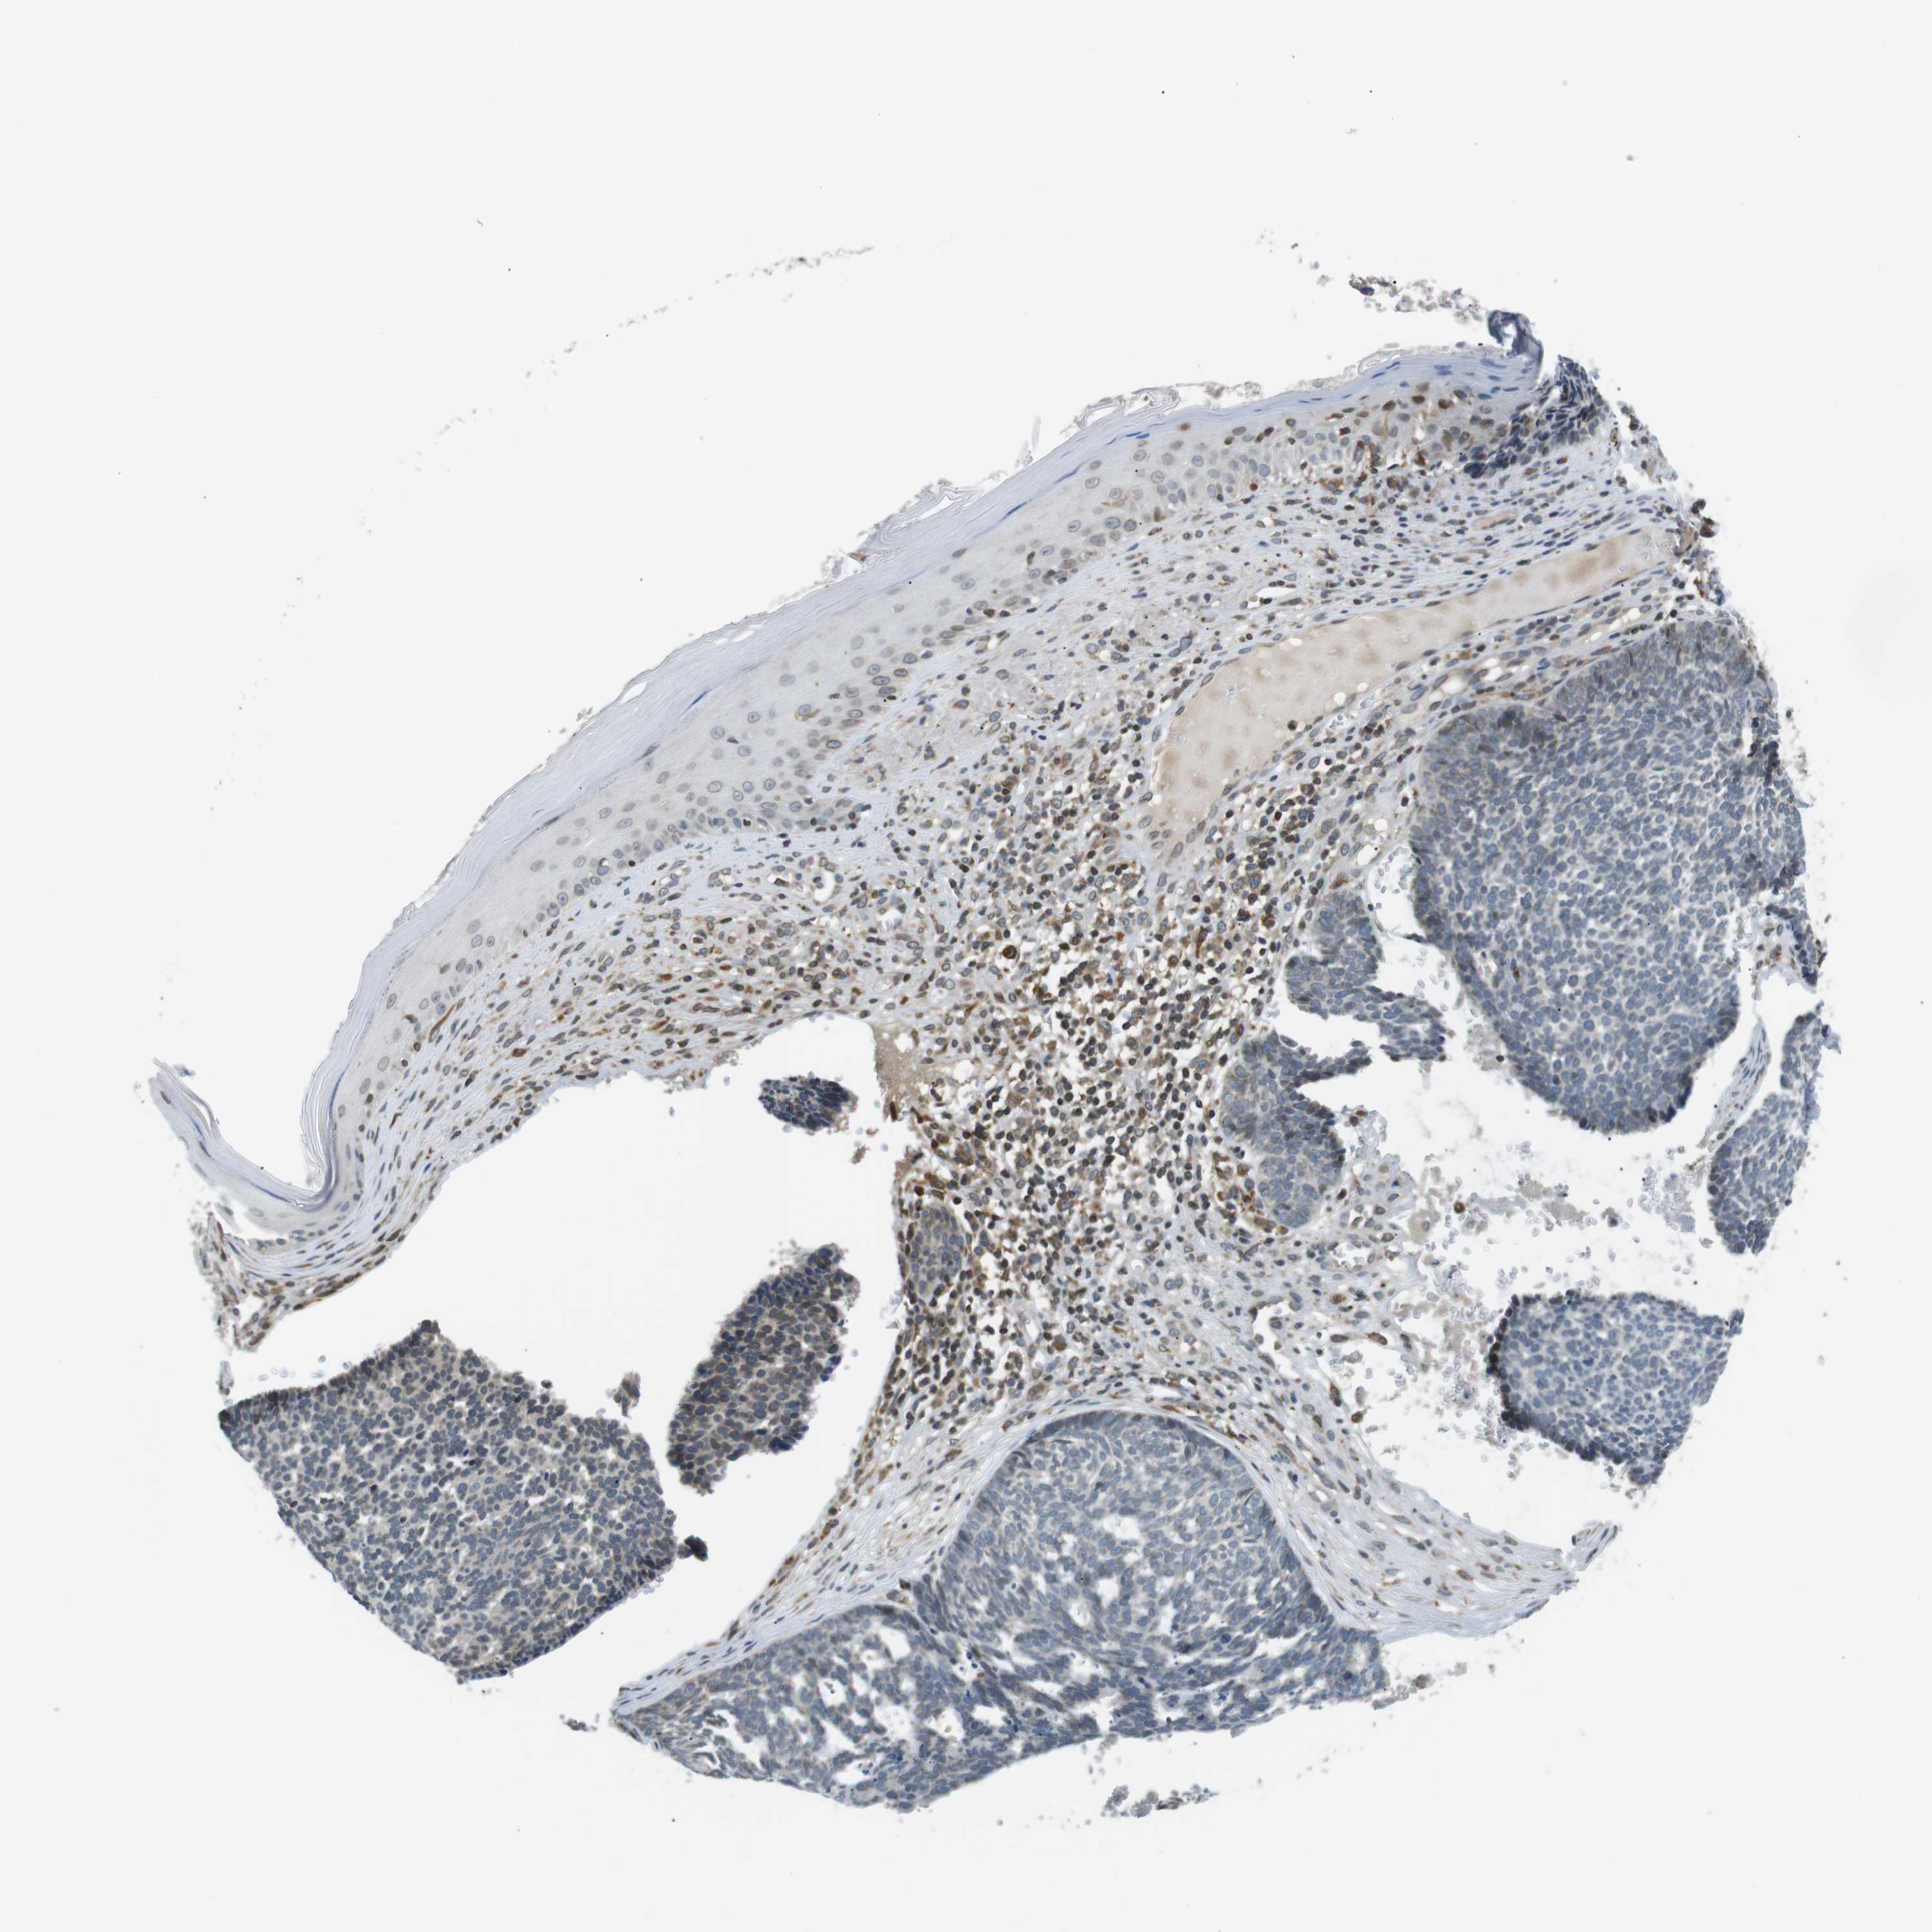

SKIN CANCER - Protein expressioni

A mouse-over function shows sample information and annotation data. Click on an image to view it in a full screen mode. Samples can be filtered based on level of antibody staining by selecting one or several of the following categories: high, medium, low and not detected. The assay and annotation is described here.

Antibody stainingi

Antibody staining in the annotated cell types in the current human tissue is reported as not detected, low, medium, or high, based on conventional immunohistochemistry profiling in selected tissues. This score is based on the combination of the staining intensity and fraction of stained cells.

Each image is clickable and will lead to virtual microscopy that enables deeper exploration of all samples and also displays staining intensity scores, fraction scores and subcellular localization as well as patient and tissue information for each sample.

Antibody HPA000399

Squamous cell carcinoma, NOS